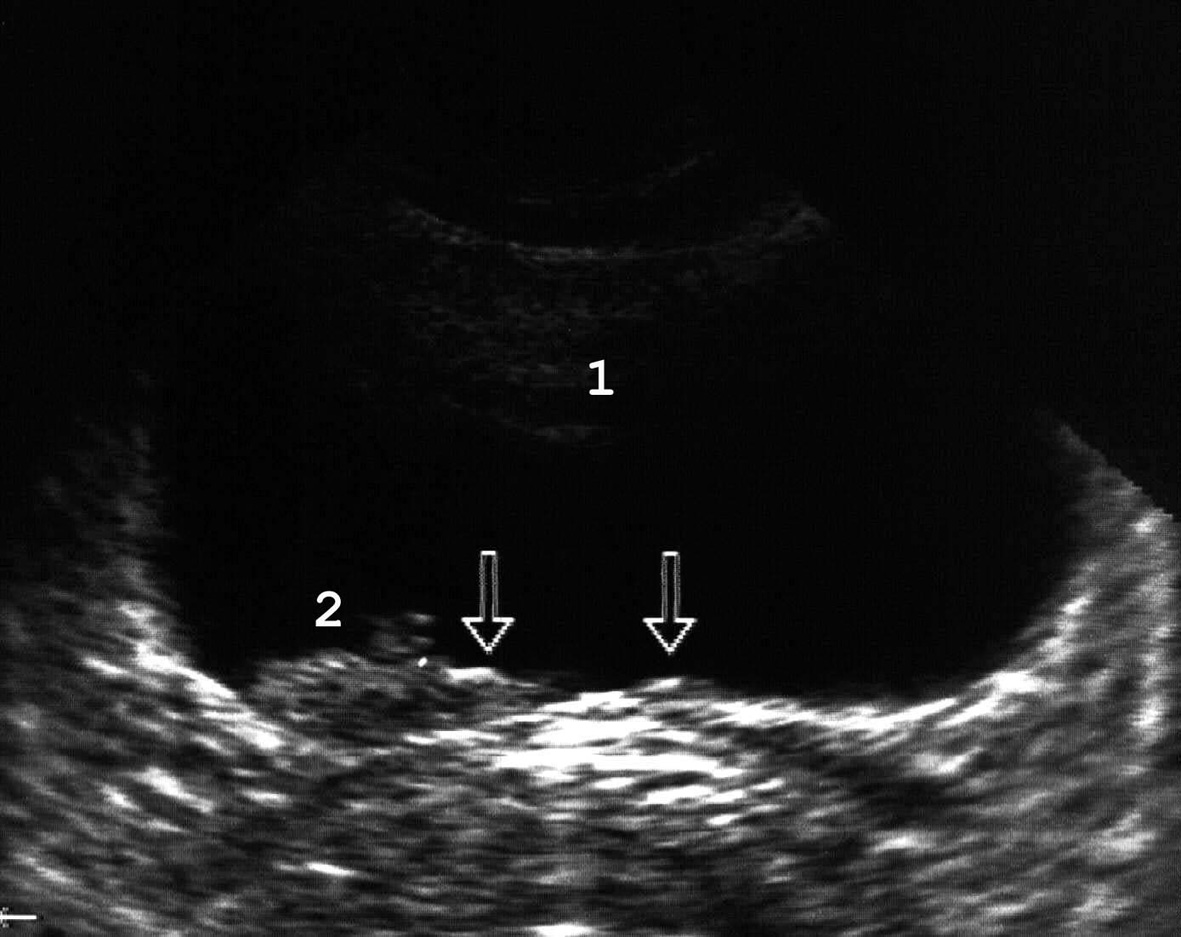

Рис. 9. Папиллярная опухоль области треугольника мочевого пузыря, расположена рядом с устьем правого мочеточника: 1 − мочевой пузырь; 2 − опухоль, стрелками указаны устья мо¬че-точников. (Поперечное сканирование, секторный датчик 3,5 МГц, “Siemens SL-2”).

Наиболее часто встречаются папиллярные опухоли мочевого пузыря (рис. 9). Доброкачественные папилломы (типичная и атипичная папиллярные фиброэпителиомы) при сонографии выглядят как полипоподобные ворсинчатые новообразования до 1 см высотой, располагаются чаще на боковых стенках и отличаются толщиной ножки и акустической плотностью. Папиллярный рак внешне напоминает папиллому, однако крупнее ее и располагается на широком основании. Часто определяются признаки солевой инкрустации опухоли. Сонографический дифференциальный диагноз между доброкачественными и злокачественными папиллярными новообразованиями при их небольших размерах чаще всего невозможен.